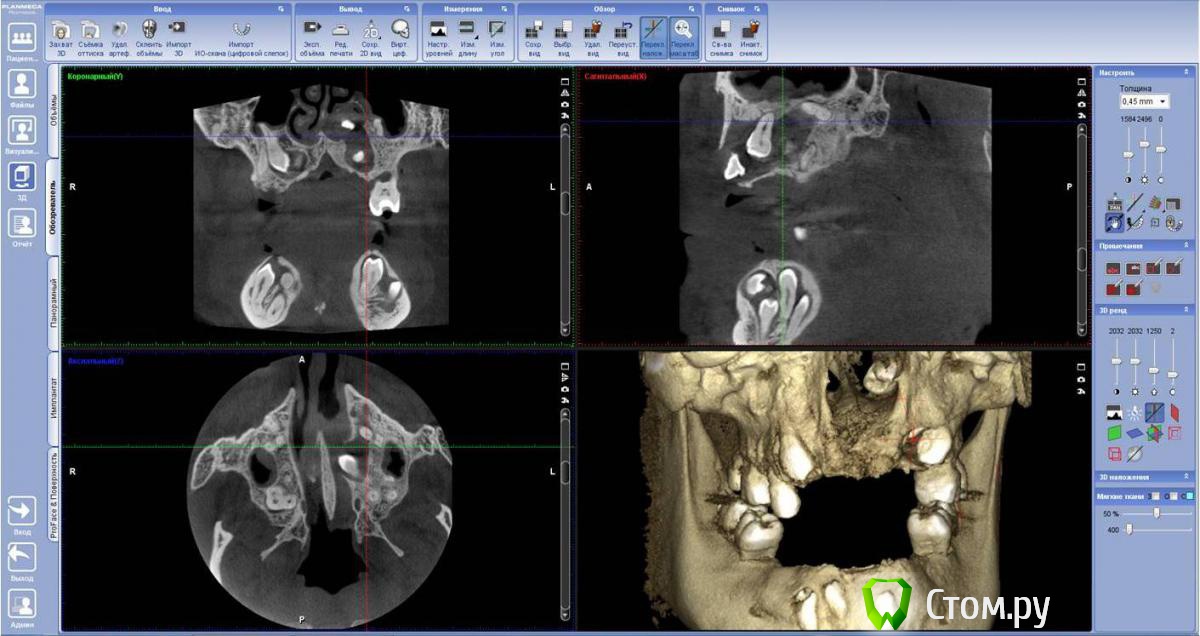

FBR Опубликовано 28 января, 2014 Поделиться Опубликовано 28 января, 2014 (изменено) Планируется протезирование на имплантатах ( в перспективе). Оперировать 1 этап (удаление зубов), планируем с ЛОРом. Изменено 28 января, 2014 пользователем FBR Ссылка на комментарий

Dr.Stein Опубликовано 28 января, 2014 Поделиться Опубликовано 28 января, 2014 Печально все это, особенно зуб в носу....Сколько лет пациенту? Ссылка на комментарий

FBR Опубликовано 29 января, 2014 Автор Поделиться Опубликовано 29 января, 2014 Красота. А сколько лет пациенту?34 года. Пока по плану с лором определяемся. Думаю убрать слева зубы с минимальной травмой кости. 25 лежит в носу и частично в кисте. Ссылка на комментарий

SergioS Опубликовано 29 января, 2014 Поделиться Опубликовано 29 января, 2014 Лечение затянется не на один год. А почему так мало то: только 25? Можно было бы все, с пазухой с правой связанные? Ссылка на комментарий